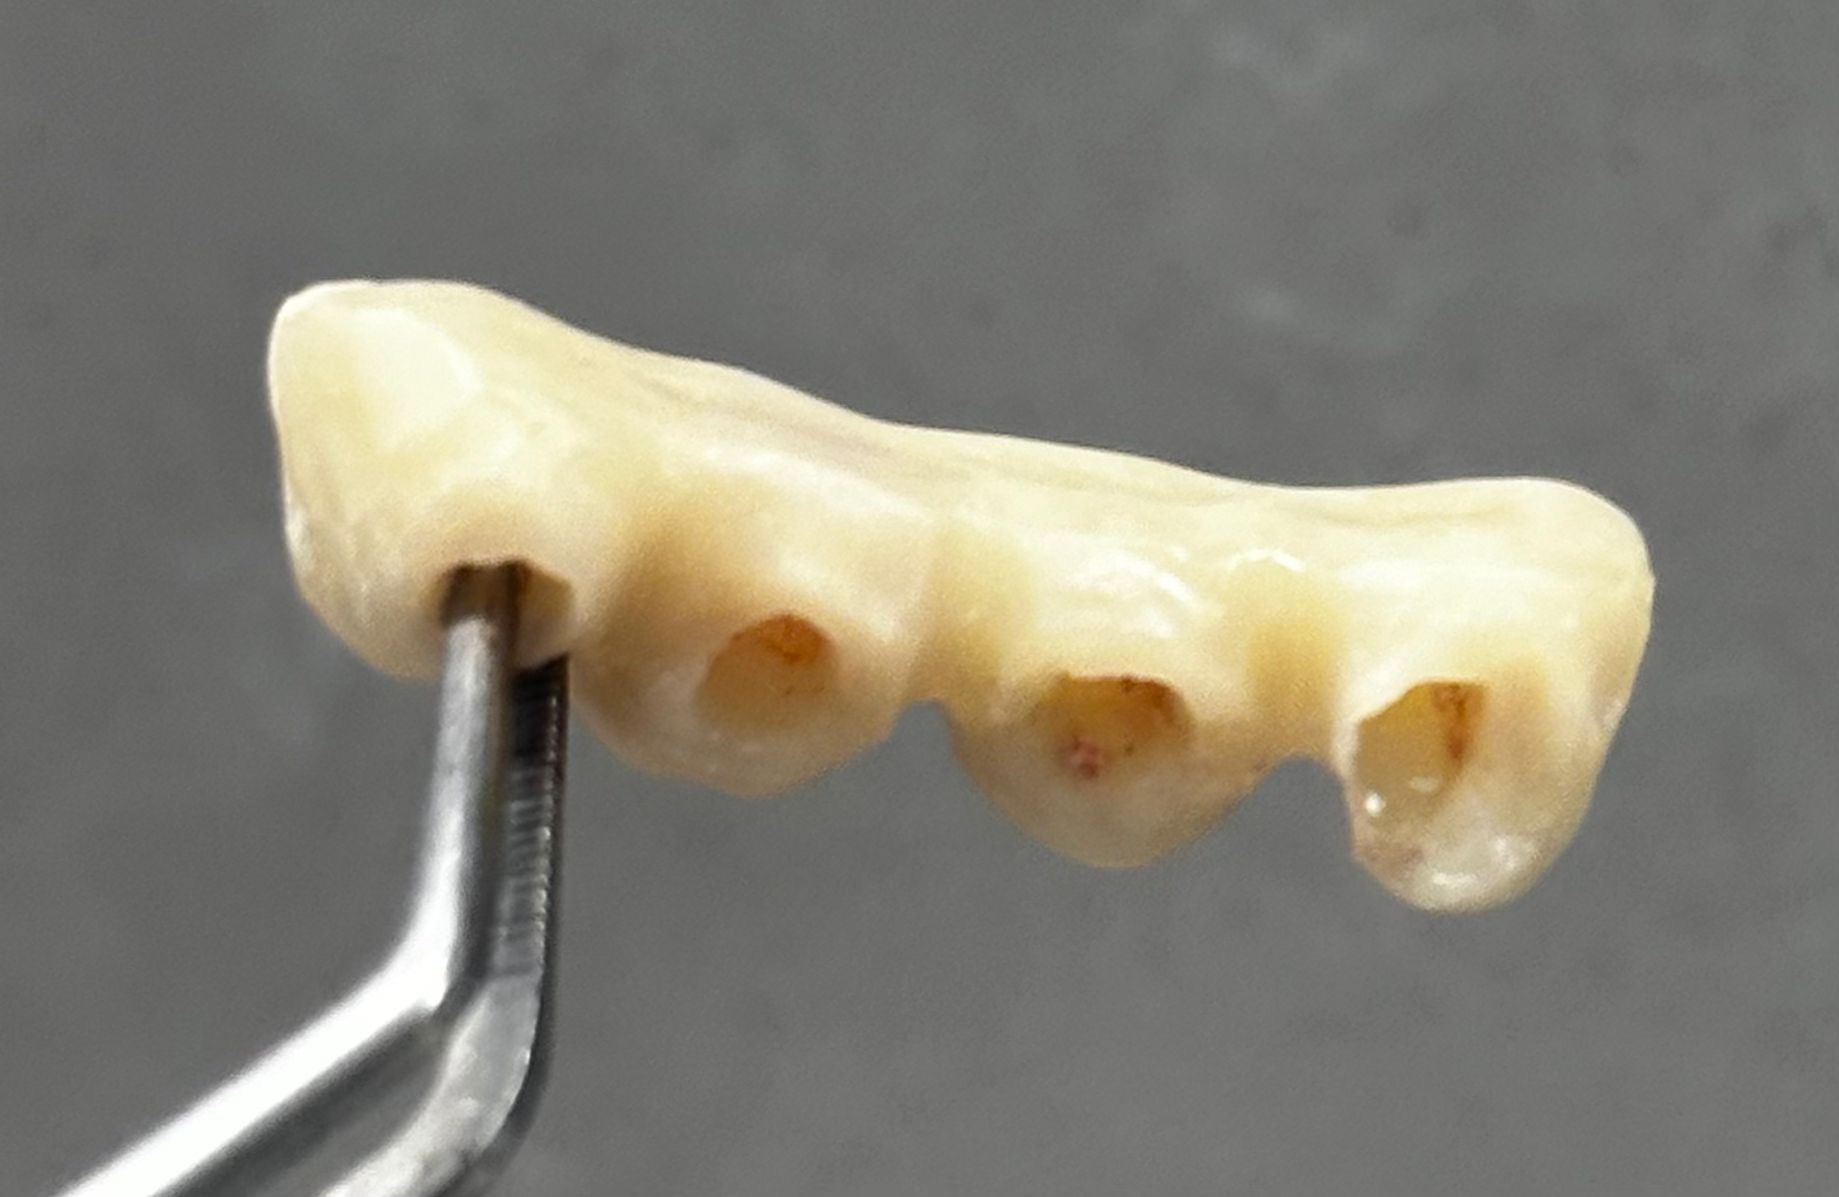

Realizamos la extracción de los cuatro incisivos superiores y, en el mismo acto quirúrgico, colocamos cuatro implantes de anclaje basal de 23 mm, buscando apoyo en el hueso cortical, el hueso más denso y estable. Además, se realizó una soldadura intraoral para rigidizar el conjunto y aportar máxima estabilidad desde el primer momento.

Se colocó un provisional de larga duración para controlar la evolución de los tejidos y, como suele ocurrir en este tipo de casos, el paciente refirió molestias mínimas y una mejoría inmediata en función, estética y bienestar.